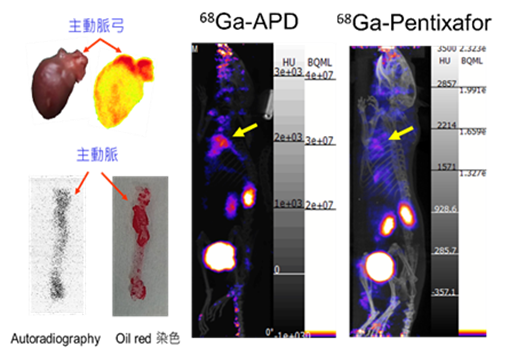

以動脈粥狀硬化模式(ApoE

)小鼠進行PET/CT造影(圖二),鎵-68-APD可在1小時內於動脈粥狀硬化病變部位產生藥物聚集,並經由腎臟、膀胱快速排泄出體外,病變部位/背景比TBR>10,優於目前國際上執行人體臨床試驗用藥鎵-68-Pentixafor;若與臨床用藥氟-18-FDG相比較,氟-18-FDG僅會在心肌產生大量藥物聚集,對於冠狀動脈的動脈粥狀硬化病變部位的專一性造影診斷效果並不理想;氟-18-NaF目前對於中、晚期病變部位產生鈣化的造影診斷僅於臨床試驗,故亦無法應用於未鈣化與不穩定斑塊的檢查。

圖二、動脈粥狀硬化造影劑鎵-68-APD於病變部位的造影效果